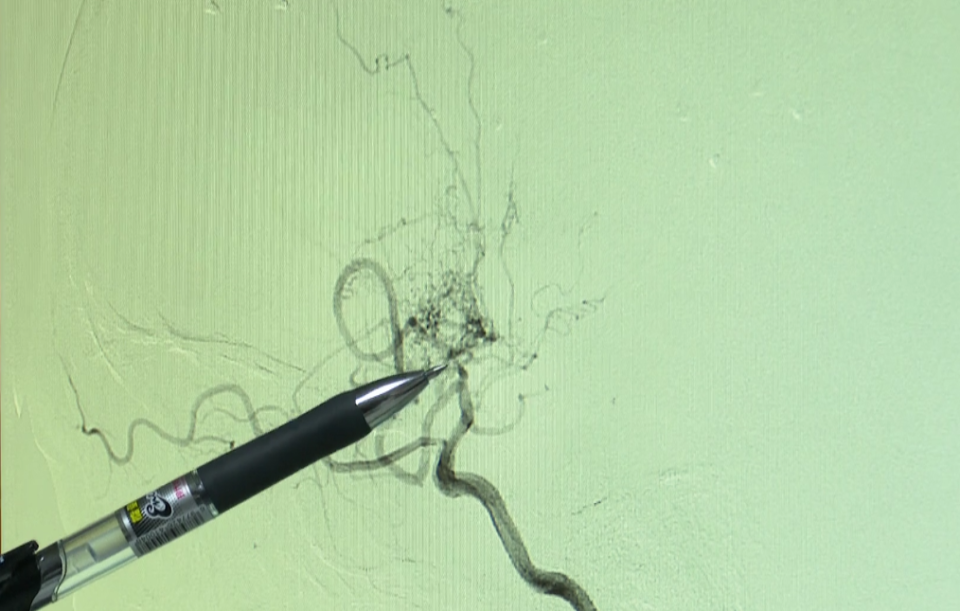

医生检查发现

瑶瑶的脑部血管影像

呈现出一团“烟雾”

而它正是脑梗的元凶

“这是大脑后动脉,到颈动脉末端这里,

大家就看不到正常的管径了,

而是一团比较乱的血管,

(形似)烧柴做饭的时候,烟囱冒出来的烟。”

据介绍,瑶瑶得的是“烟雾病,成因暂时不得而知,烟雾病会导致大脑主要血管狭窄或闭塞,而大脑为了“自救”,会代偿性生成一些血管。这些“烟雾”血管,既容易破裂引发脑出血,也可能因供血不足诱发脑梗。其中,脑缺血在儿童中尤为常见。